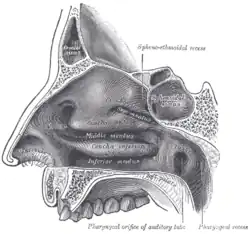

Choana (z řec. choane–nálevka[1]) čili vnitřní nozdra je zadní otvor nosní dutiny, který spojuje tuto dutinu s dutinou ústní.